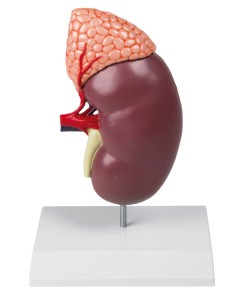

Dal cranio in 22 parti con incastri magnetici ai modelli di colonna vertebrale, da quelli di articolazioni a quelli di cuore, ogni pezzo della nostra collezione è progettato per un’immersione totale nello studio dell’anatomia umana. I nostri modelli, realizzati tramite scansioni di ossa vere, garantiscono un’esperienza tattile autentica e una fedeltà di peso quasi identica agli originali.

Essenziali per studenti e professionisti, i nostri modelli anatomici sono strumenti didattici che permettono di osservare le strutture anatomiche con precisione, eliminando la necessità di dissezioni o studi invasivi. Sono inoltre utili per spiegare ai pazienti le patologie, rendendo la comunicazione più efficace e risparmiando tempo prezioso.